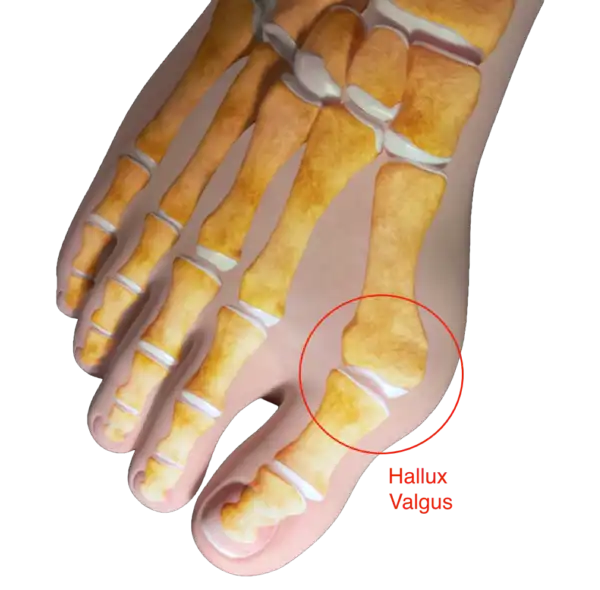

- Chirurgia della spalla, gomito, polso, caviglia e piede.